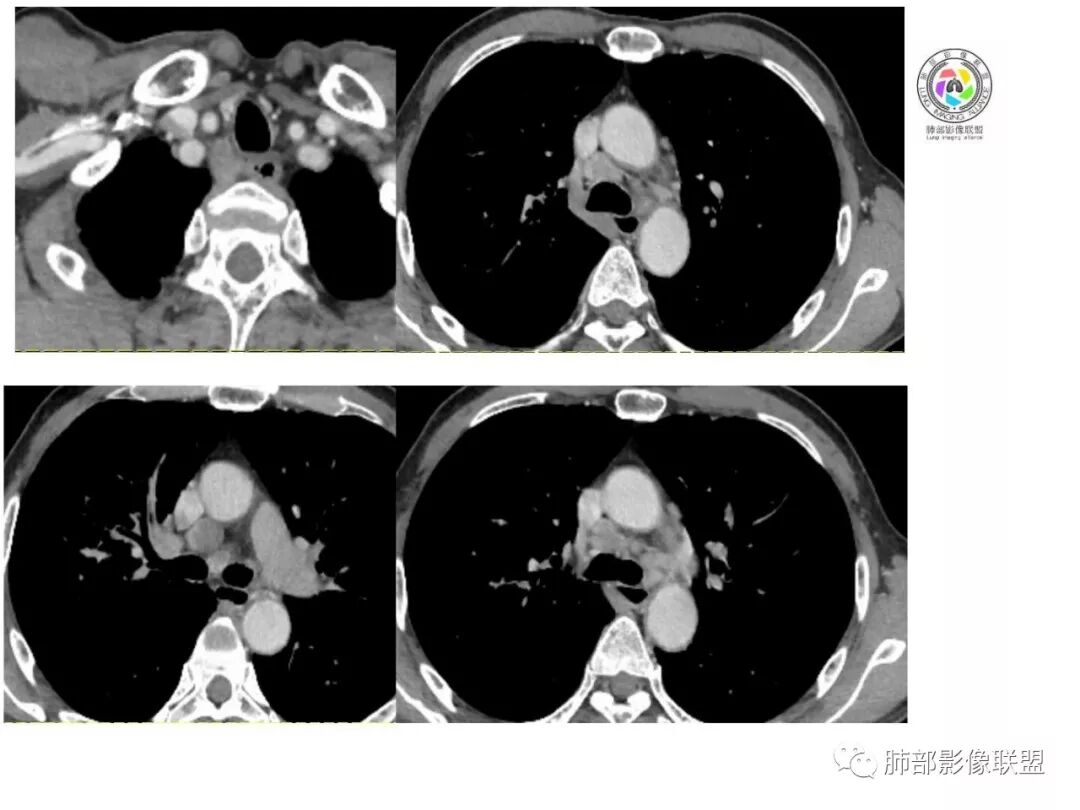

右肺巨大肿块,跨叶生长,其内见大片状坏死,坏死边界不清,血管进入,边缘受侵,病灶边缘可见毛刺及分叶,病灶强化方式速升速降,纵隔内见坏死强化淋巴结,周围肺叶小叶间隔结节样增厚,考虑恶性腺癌并淋巴结转移及癌性淋巴管炎,鉴别肉瘤。

右肺中叶可见类圆形软组织密度肿块影,右肺中叶外侧段支气管狭窄截断。肿块密度不均,边缘毛燥不规则,可见毛刺。远侧肺内可见网格条索影。增强后可见不均匀强化。纵隔淋巴结肿大,部分融合。考虑右肺恶性病变,鳞癌>腺癌,并纵隔淋巴结转移。

患者中老年男性,体检发现肺部占位。

胸CT:右肺中叶实性占位性病变,呈膨胀性生长,对斜裂明显挤压,右肺中叶外侧段阻塞,并在边缘可见分叶、毛刺、棘突样改变,胸膜牵拉;增强可见病灶明显强化,可见边缘模糊血管影,病灶内可见大片状低密度区,隆突下可见肿大淋巴结。

诊断考虑:恶性病变。

右肺巨大肿块,横跨上中下三叶,主体在中叶,外侧段近端支气管截断,膨隆分叶,毛刺,网格,淋巴结大,不均匀强化,湖泊样坏死,考虑恶性,低分化鳞癌>腺

右肺肿块,横跨上中下三叶,主体在中叶,外侧段近端支气管截断,膨隆分叶,毛刺,网格,淋巴结大,不均匀强化,有坏死,鳞癌?

老年男性,查体发现,右肺上叶中叶巨大肿块,有分叶,周围有条索影,支气管受压推移,内有大片及小灶坏死,坏死边界有的清楚有的不清,周围明显强化,纵隔有肿大淋巴结,跨叶生长,考虑恶性,腺癌或肉瘤样癌

右肺中叶可见类圆形软组织密度肿块影,支气管狭窄截断。肿块密度不均,边缘毛燥不规则,可见毛刺。增强后可见不均匀强化。纵隔淋巴结肿大,部分融合。考虑右肺恶性病变,鳞癌?

老年男性,右肺上叶可见一团块影,边界清,有膨隆,有凹陷,棘突,有分叶,密度不均匀,周边可见癌性淋巴管炎,跨叶裂,支气管阻塞?受压?狭窄,纵隔淋巴结肿大,考虑恶性,腺癌可能

右肺跨上叶与中叶一实性肿块影,中叶外侧段支气管堵塞,肿块有明显分叶、毛刺、棘突样改变,胸膜牵拉,周围有小花小草;增强可见病灶明显强化,病灶内可见大片状低密度区,以外侧为主,隆突下可见肿大淋巴结,恶性,考虑鳞癌可能。

老年人,右肺上叶软组织肿块,边界清晰,有浅分叶,右肺上叶支气管受阻,增强后病灶边缘强化,内部似有延迟强化,内见血管造影征,其血管边缘毛糙,纵隔可见增大淋巴结,考虑恶性肿瘤,无明显阻塞性肺炎和不张,考虑腺癌或腺鳞癌伴纵隔淋巴结转移

老年男性,体检发现右肺巨大肿块,右肺跨叶生长,可见支气管截断,边缘见分叶,毛刺,右肺支气管不通,增强后边缘强化,内部示大片低密度坏死区,边界不清,周围肺组织小叶间隔增厚,纵隔见多发肿大淋巴结。考虑为恶性并淋巴结转移。

右肺肺门肿块,自肺门向外延伸,外大内小,肿块呈长条状,平行支气管,近段支气管不规则堵塞,支气管无扩张壁无增厚,平扫密度均匀,增强后可见不规则坏死,病灶跨叶裂生长,纵隔淋巴结肿大,中老年男性,体检发现,无症状,考虑:恶性鳞癌,鉴别结核

老年男性,右肺跨裂生长团块灶,边缘浅分叶,内不均匀强化,无强化坏死区较多,可见支气管截断,周围阻塞性炎症,考虑恶性肿瘤可能,慢性肺脓肿待排

老年男性,右肺不规则跨叶肿块,有分叶,相邻支气管阻断,强化不均有低密度坏死区,坏死区边界较清,类似湖泊样,内见血管穿行,造影征,病灶远端可能有阻塞性炎症,总体考虑鳞癌。

患者中老年男性,体检发现右肺占位。血常规轻度贫血,AFP、CEA正常,肝肾功能、血糖、血脂、心肌酶、电解质正常。胸部CT:右肺中叶巨大肿块灶,垮叶生长,可见分叶、毛刺、血管集束、支气管截断征象,远端周围可见小叶间隔增厚,增强轻度强化,内可见低密度坏死区,综合淋巴结肿大,且可见淋巴结内似低密度灶。综合考虑恶性,鳞癌并癌性淋巴管炎可能大。鉴别结核、腺癌。

胸CT:右肺中叶团块样实性占位,边缘膨隆,中叶外侧段阻塞,病灶可见深分叶、棘突,胸膜牵拉;增强不均匀强化,可见边缘模糊血管影,病灶内大片状低密度区,纵隔多发肿大淋巴结。

诊断考虑:恶性病变,鳞?大细胞?鉴别:TB

右肺中叶巨大肿块,外侧段近端支气管截断,横跨上中下三叶,主体在中叶,膨隆分叶,毛刺,网格,淋巴结大,不均匀强化,伴阻塞性肺炎及肺不张,湖泊样坏死,考虑恶性,鳞癌可能性较大

右肺上叶肿块,跨叶生长,分叶,支气管截断,周围支气管受压推移,内有大片坏死,周围小叶间隔增厚,纵隔淋巴结肿大,明显强化,考虑肉瘤样癌。鉴别腺鳞癌。

病灶主体位于右肺中叶,跨上、下叶,分叶毛刺,外侧段支气管堵塞,大片坏死,边界不清,内见血管进入,增强快进快出,纵隔淋巴结肿大,小叶间隔增厚,恶性,腺癌或肉瘤样癌可能。

右肺门旁肿块,形态不规则,跨叶生长,近段支气管不规则堵塞,支气管局部增厚,密度欠均匀,增强后可见不规则坏死,纵隔淋巴结肿大,中老年男性,体检发现,考虑:恶性鳞癌